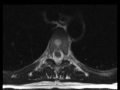

Typical and Atypical Hemangioma

This is a case demonstrating the features of typical and atypical hemangioma. Within the T2 vertebral body, there is scattered T1-hyperintense signal and prominent vertical striations. On the sagittal T2 and STIR-weighted images, there is redemonstration of hyperintense signal abnormality in the T2 vertebral body with an additional rounded hyperintense lesion in the T5 vertebral body. The contrast enhanced images demonstrate enhancing lesions in the T2 and T5 vertebral bodies. The imaging findings are of a typical hemangioma at the T2 vertebral body and an atypical hemangioma at the T5 vertebral body. Hemangioma are common benign benign vascular malformations. While the lesions are usually confined to the osseous elements, there may be epidural components.